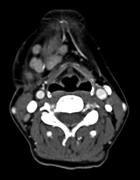

Kimura's disease: an uncommon cause of head and neck masses with potentially serious sequelae

Alexander M. Bobinskas and others

Journal of Surgical Case Reports, Volume 2015, Issue 10, October 2015, rjv131, https://doi.org/10.1093/jscr/rjv131